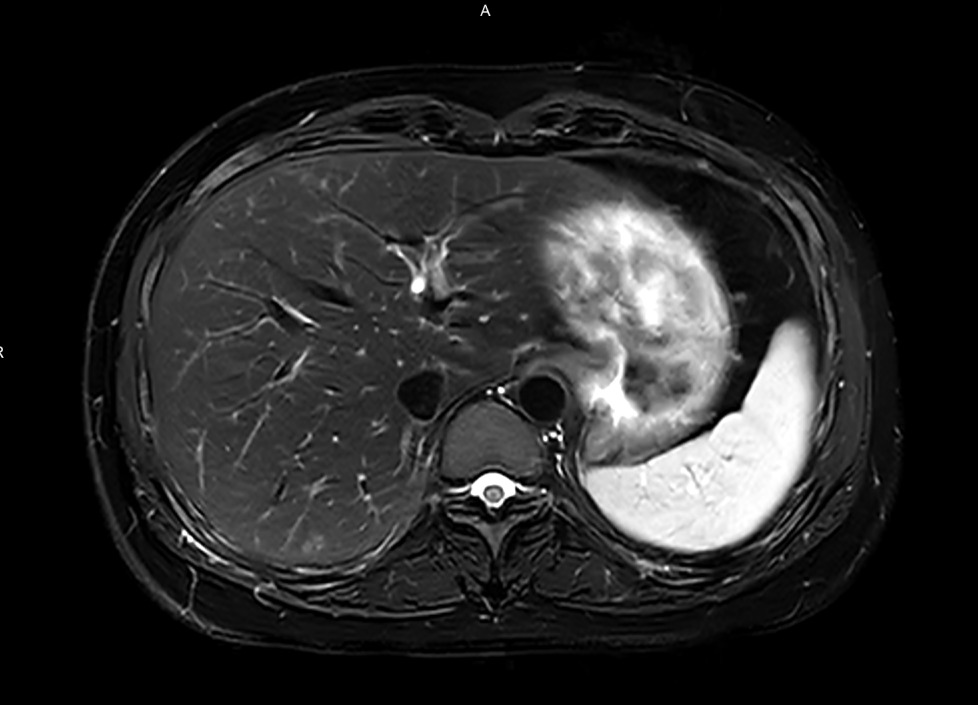

ABD T2